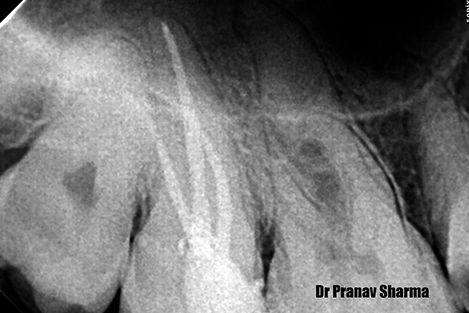

Xray